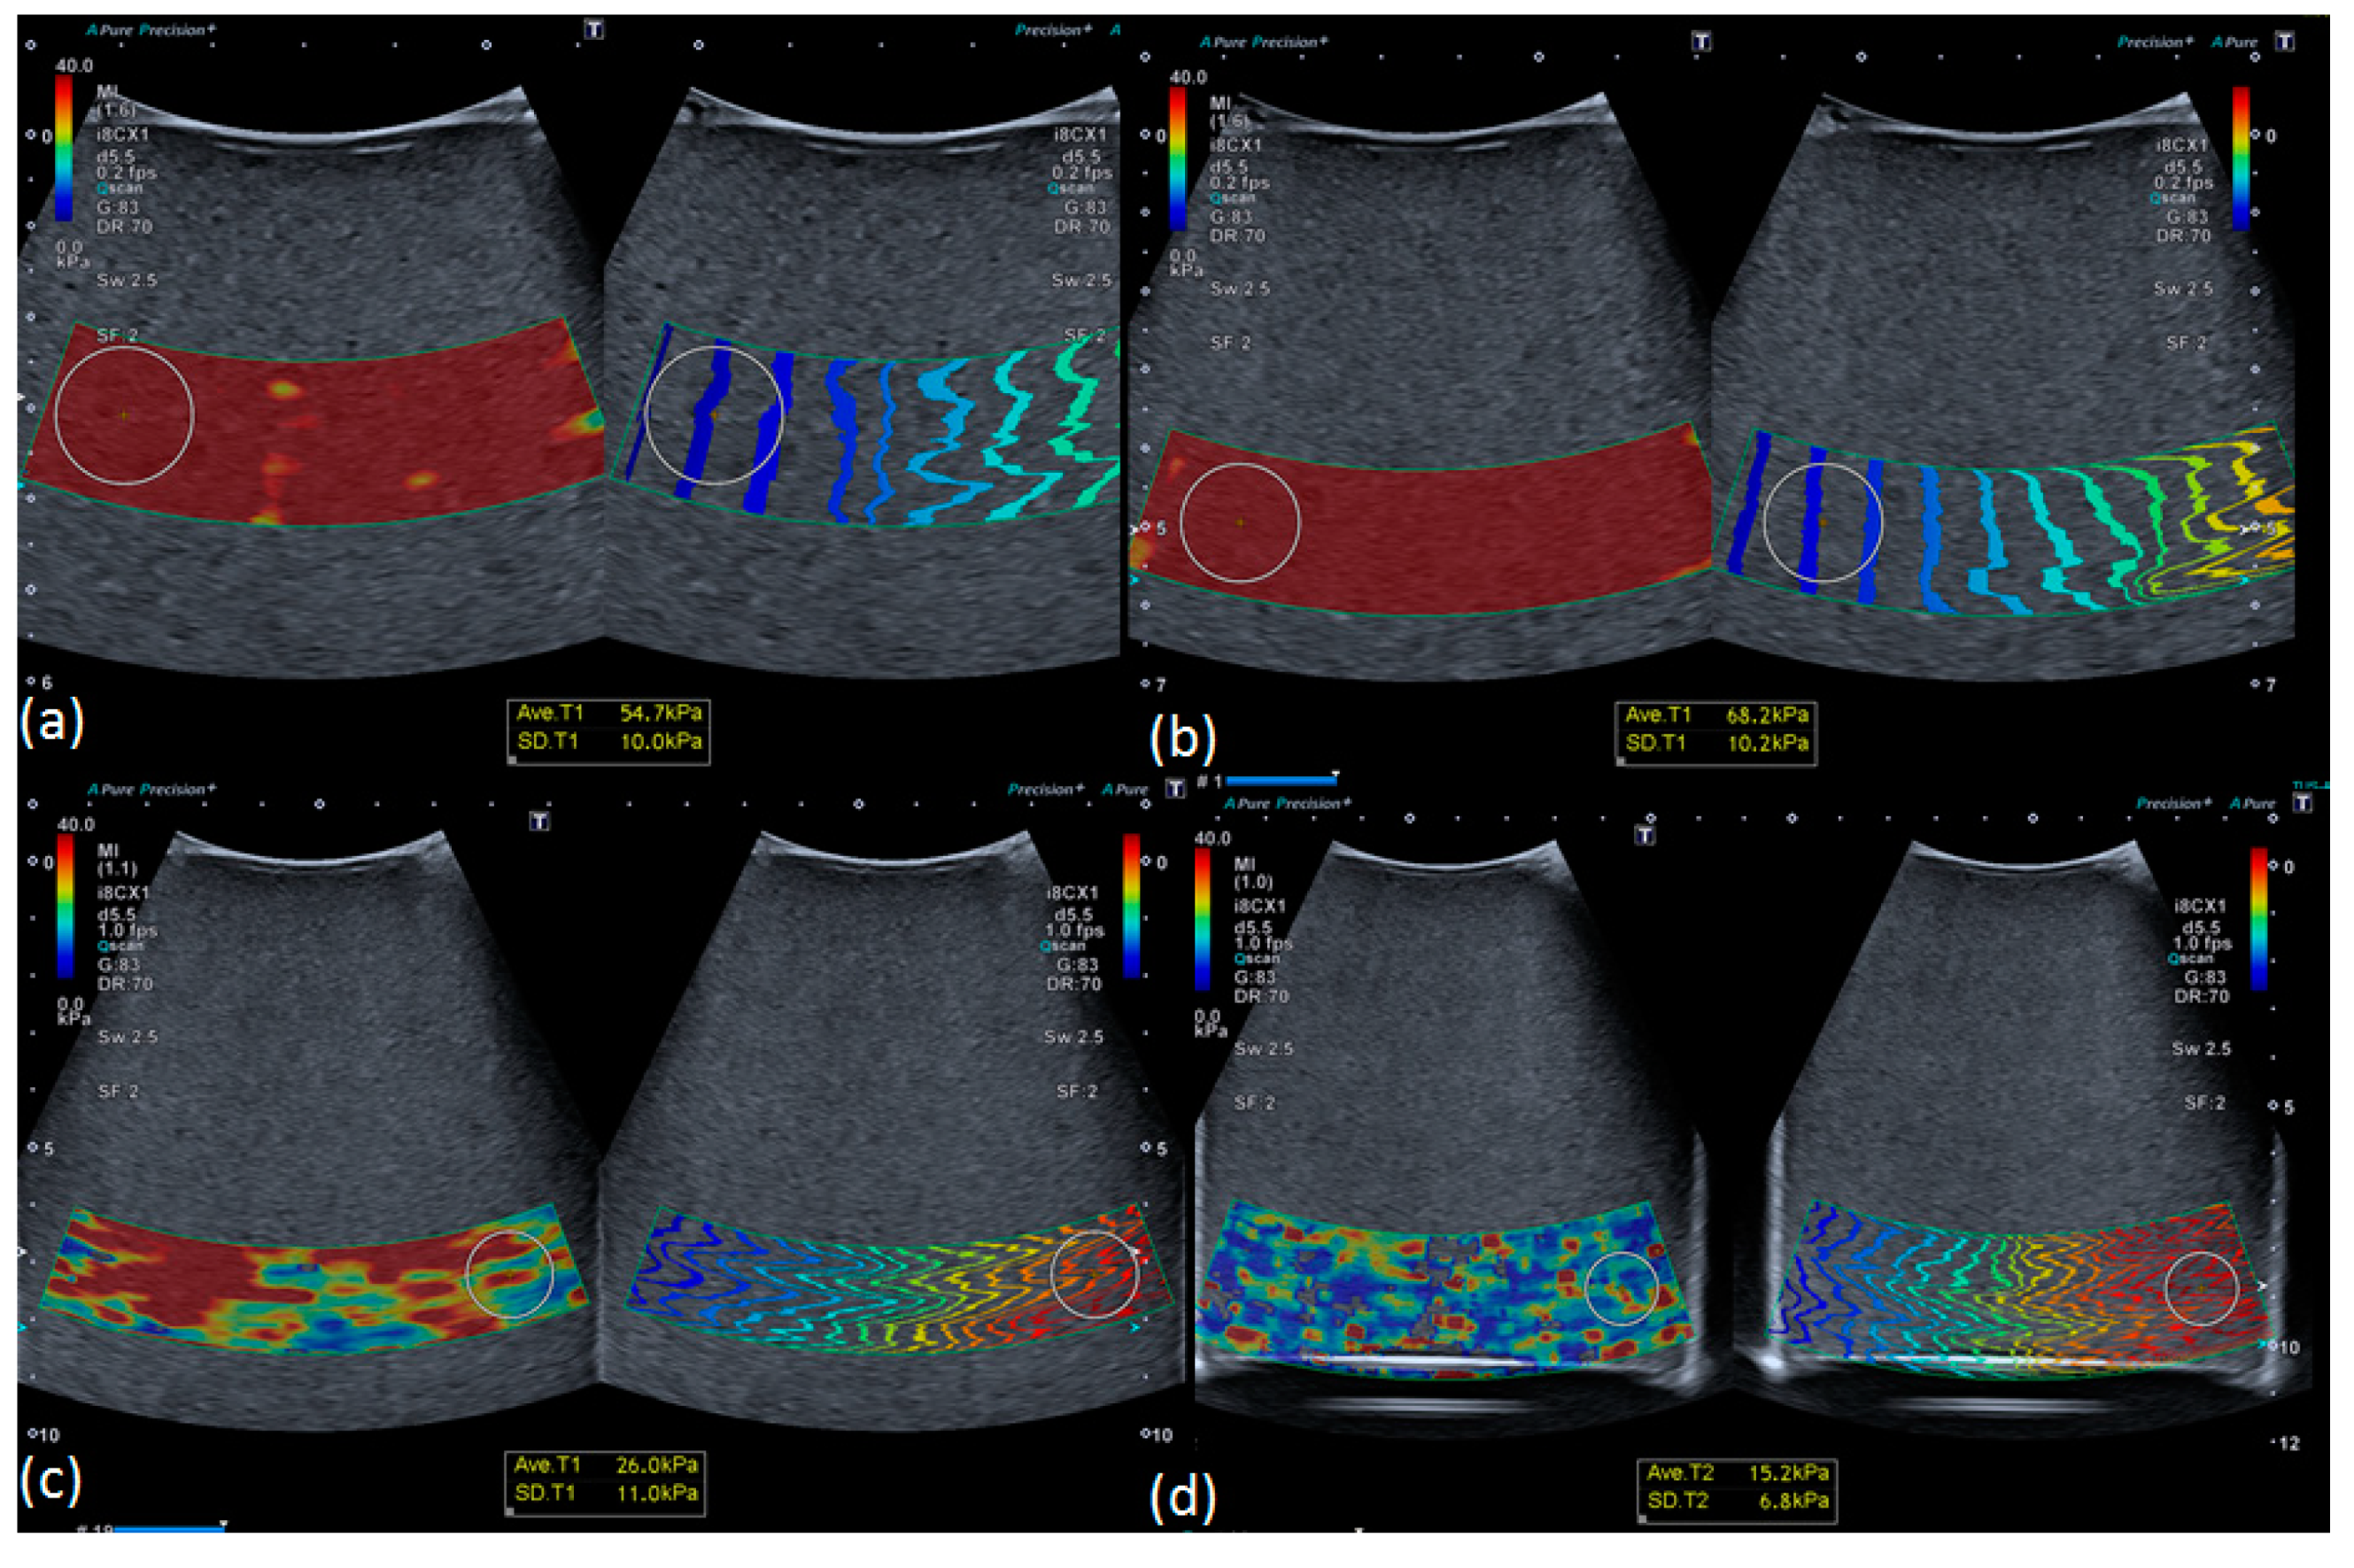

3.2. Influence of Depth on Measured Stiffness